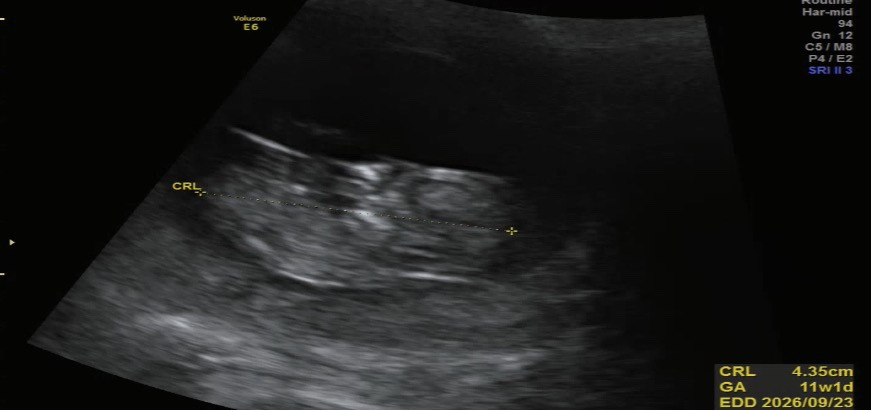

임신 11주차 4.35cm 무럭무럭 잘 자라는 금복이ㅎㅎ